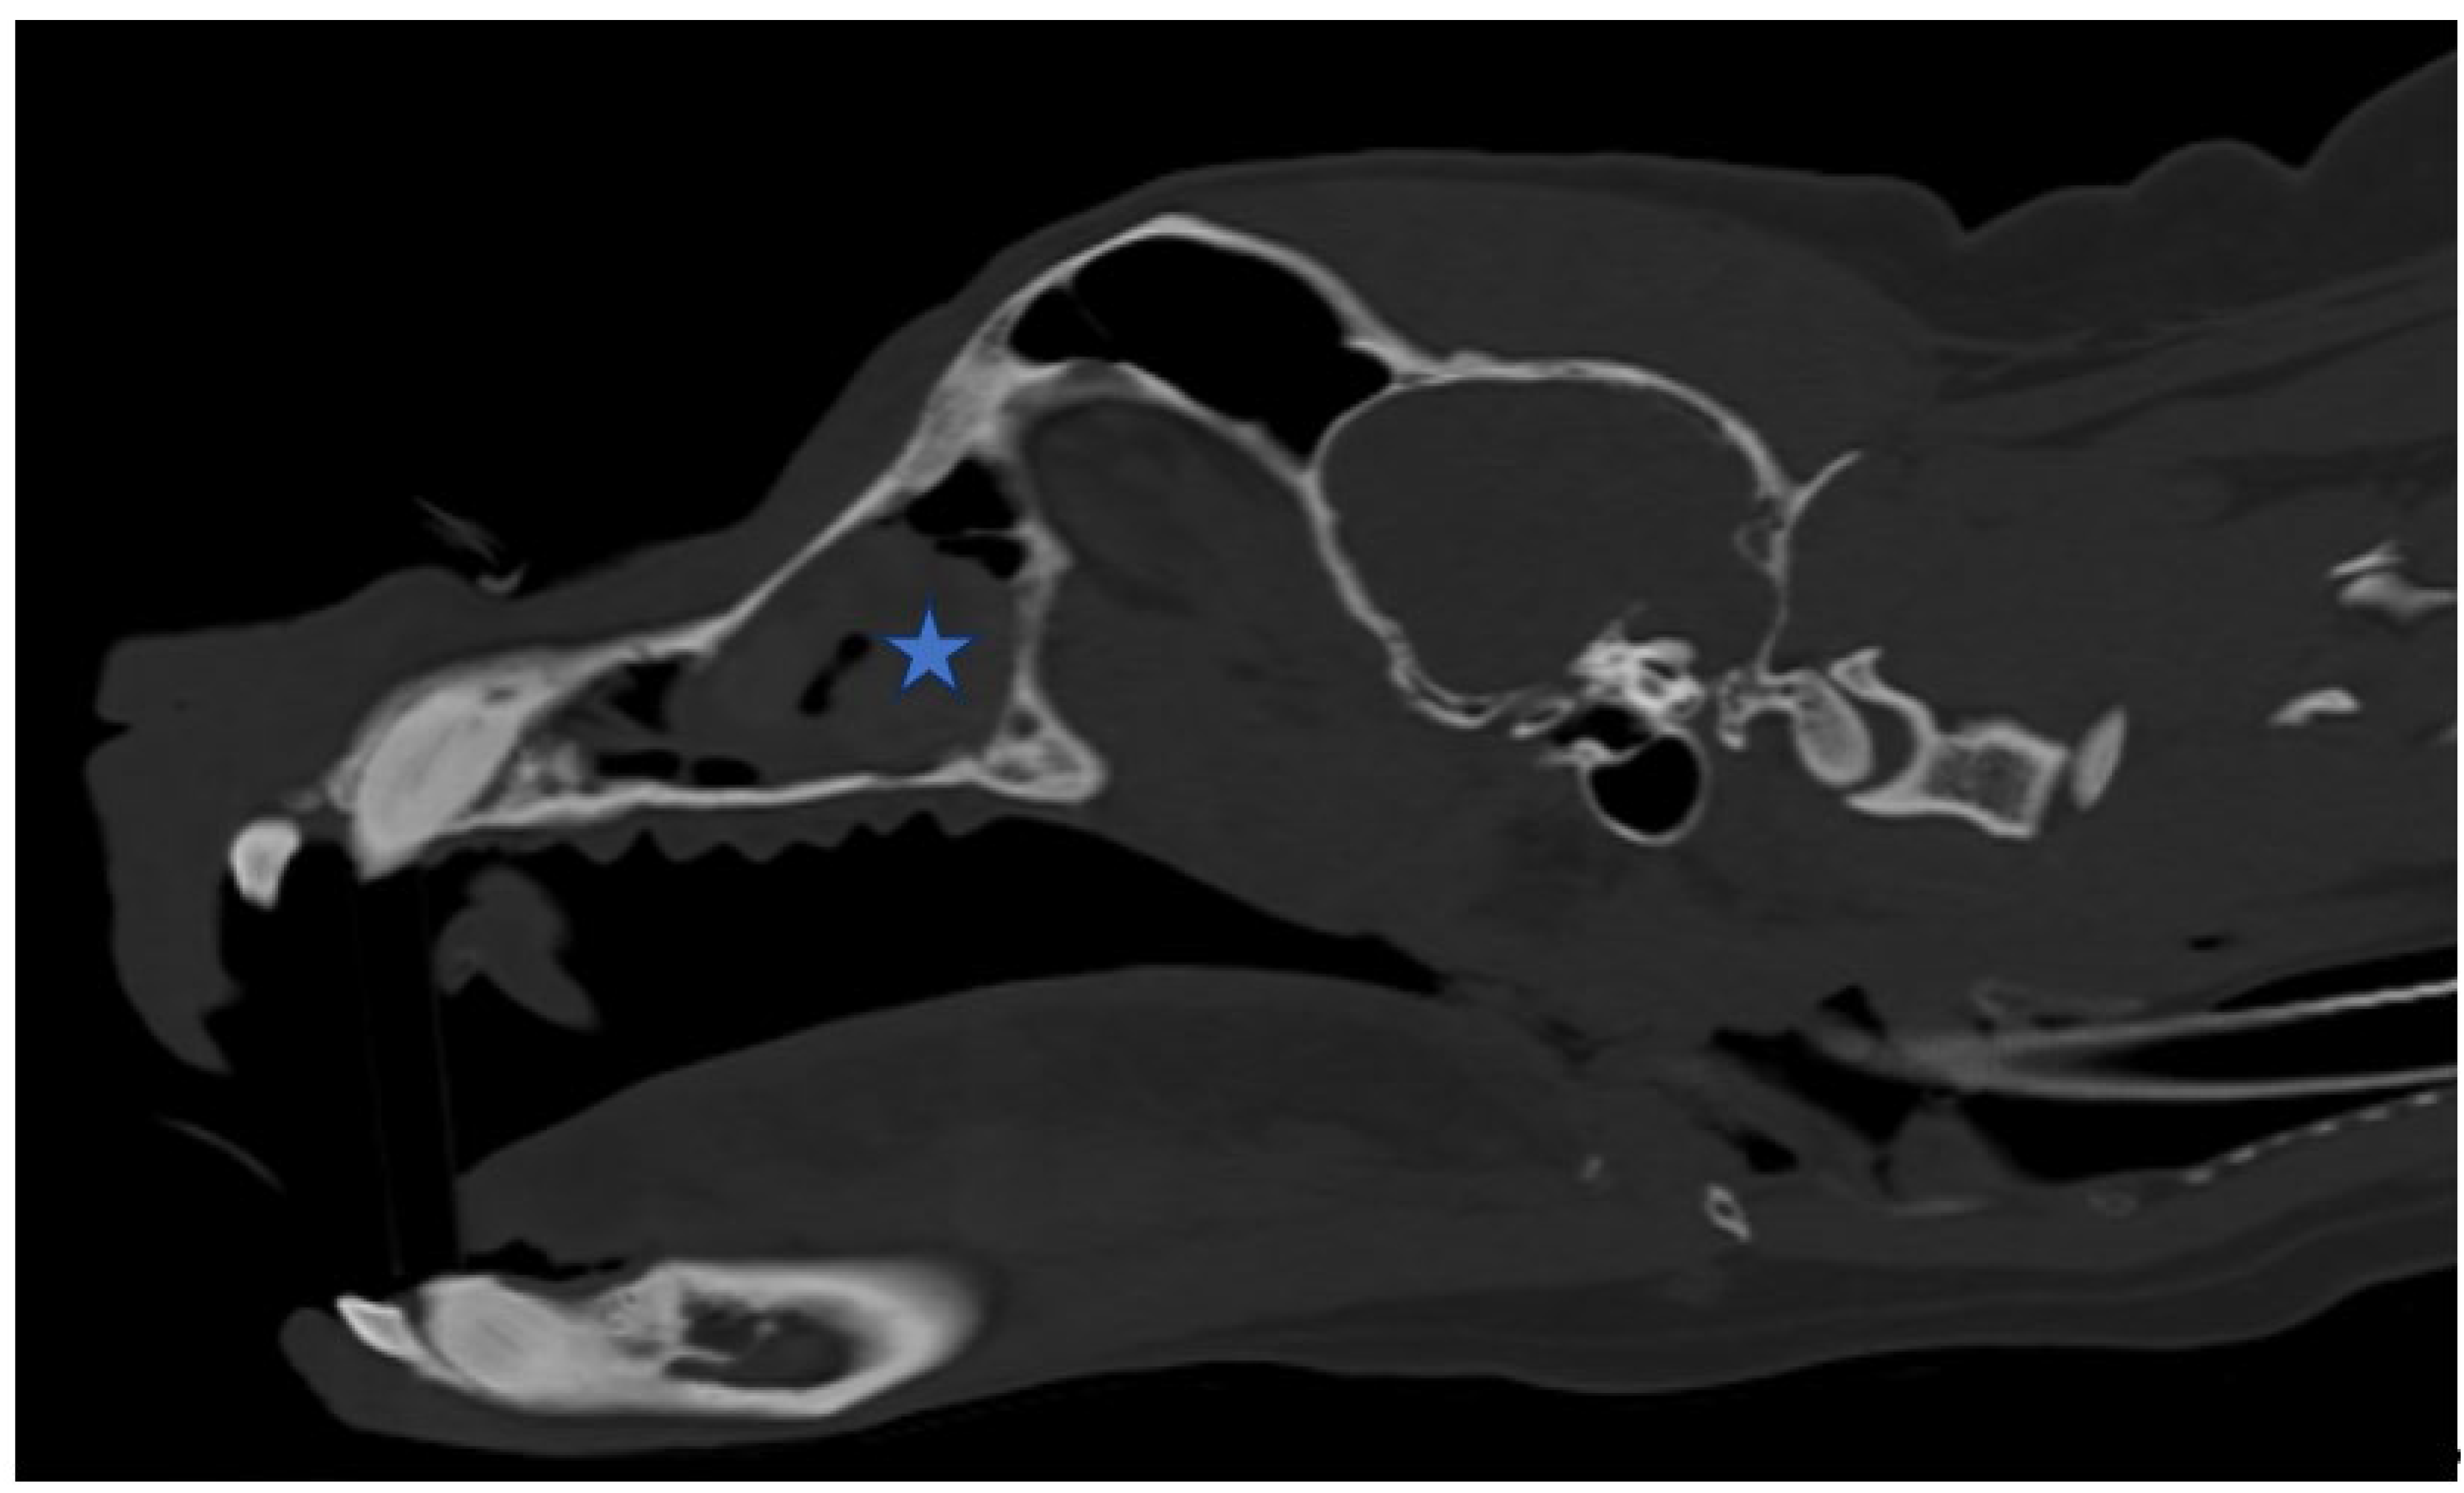

Figure 3. (A,B). Sagittal view of CT scan of skull The size of the nasal tumor decreased significantly (Asteroid).